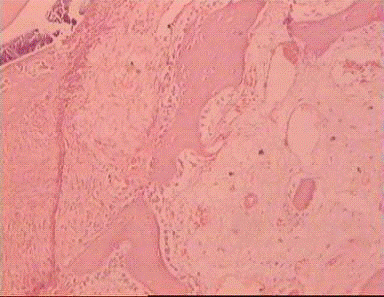

Морфологически на 30 сут. эксперимента в зоне дефекта обнаруживается первичное костное сращение с образованием соединительнотканной мозоли с участками хондроидного строения, очаговым отложением кальция, единичными зрелыми и большим количеством незрелых костных балок. Периостально слабо выраженное разрастание соединительной ткани с умеренной лимфо-плазмоцитарной инфильтрацией (рис. 8).

.

Рис.8. В межотломковой щели разрастание соединительной ткани с участками хондроидного строения, отложением кальция, новообразованием преимущественно незрелых костных балок. Окраска гематоксилином эозином. Увеличение х 200.